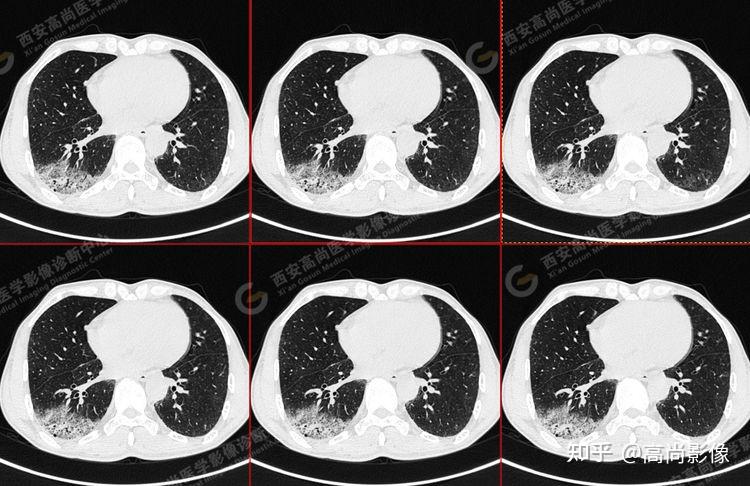

pet/ct病例—肺粘液腺癌,历经3年余终确诊【西安高尚医学影像诊断中心